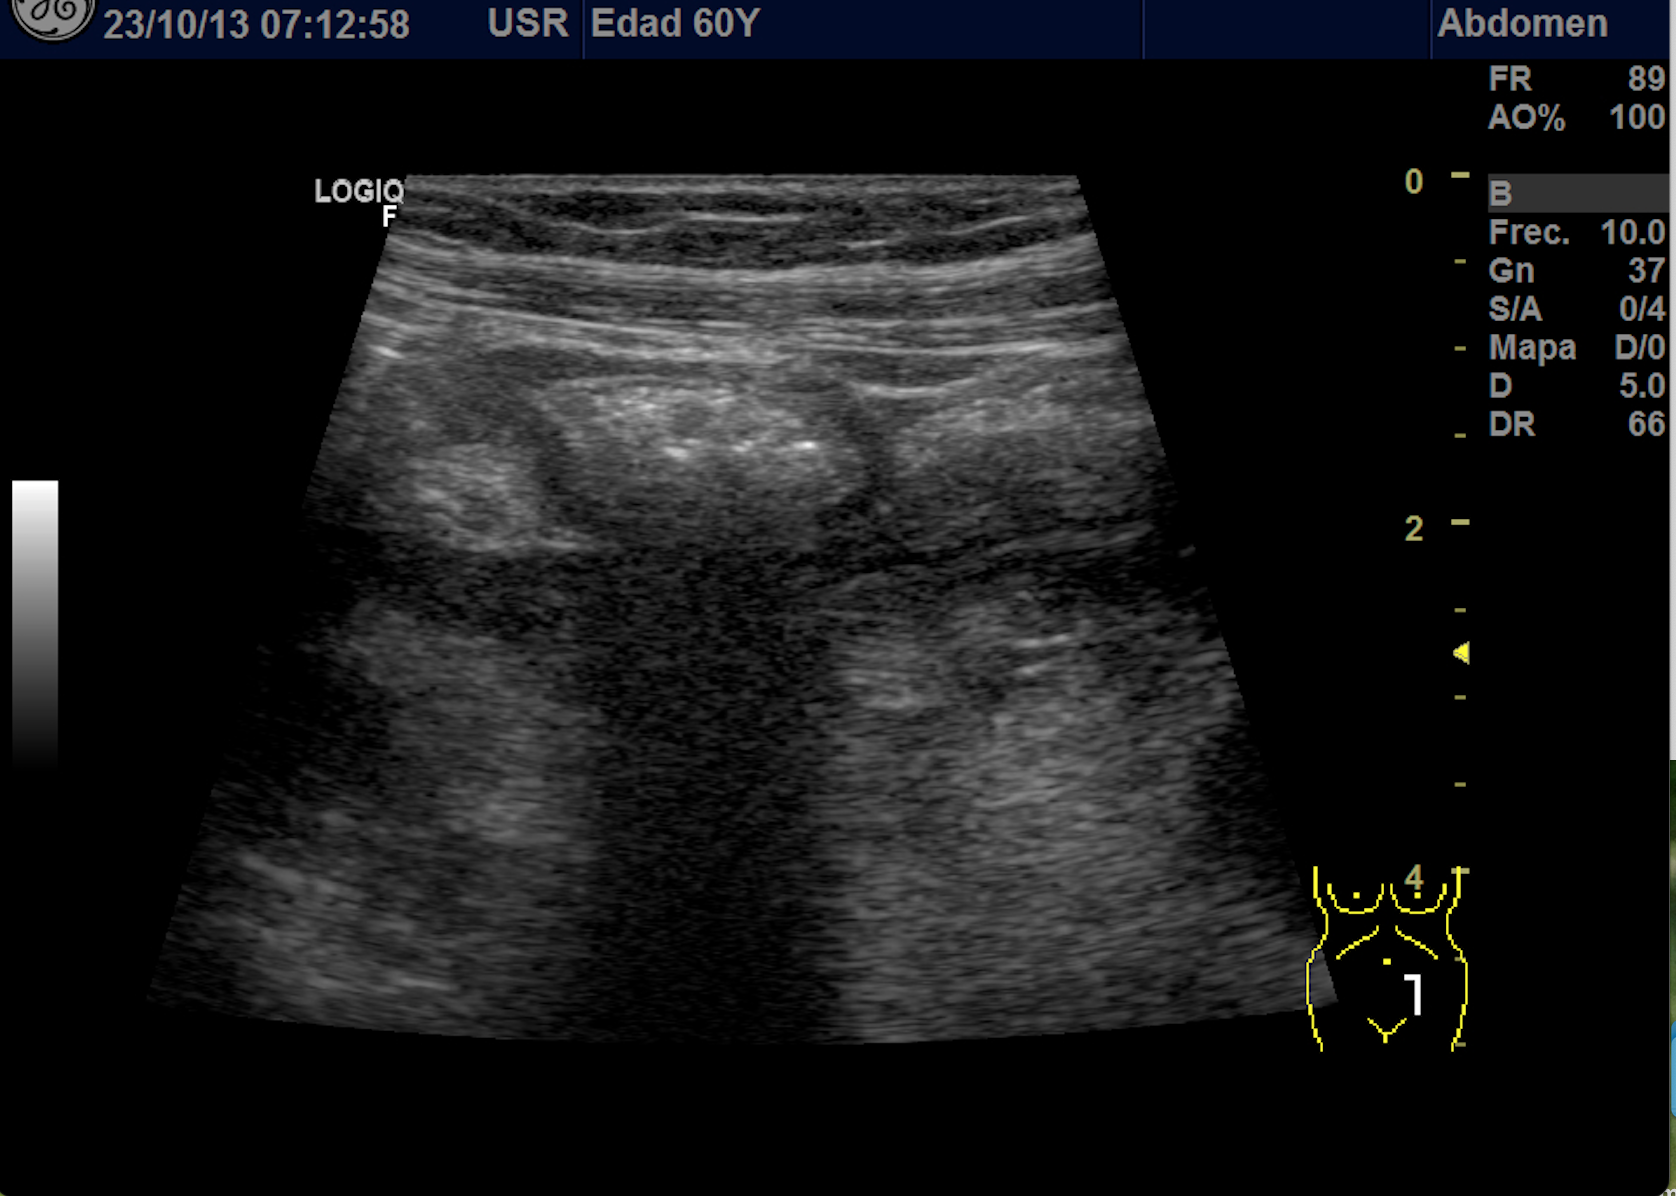

Hallazgos ecográficos

Se explora FII-hipogastrio y en el punto de más dolor se observa engrosamiento de asas de intestino grueso sin peristaltismo y con signos de edema de la grasa adyacente. No líquido libre.

También se realiza ecografia en urgencias del hospital.

En el hospital se realiza una nueva ecografía en el servicio de radiología confirmando el diagnóstico de sospecha: diverticulitis aguda en sigma distal sin datos de complicación. Hinchey 1A.